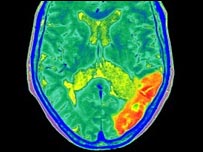

Taxa de mortalidade por derrame é maior em fins-de-semana

Cérebro com derrame

Pesquisadores canadenses analisaram taxa de mortalidade por derrame